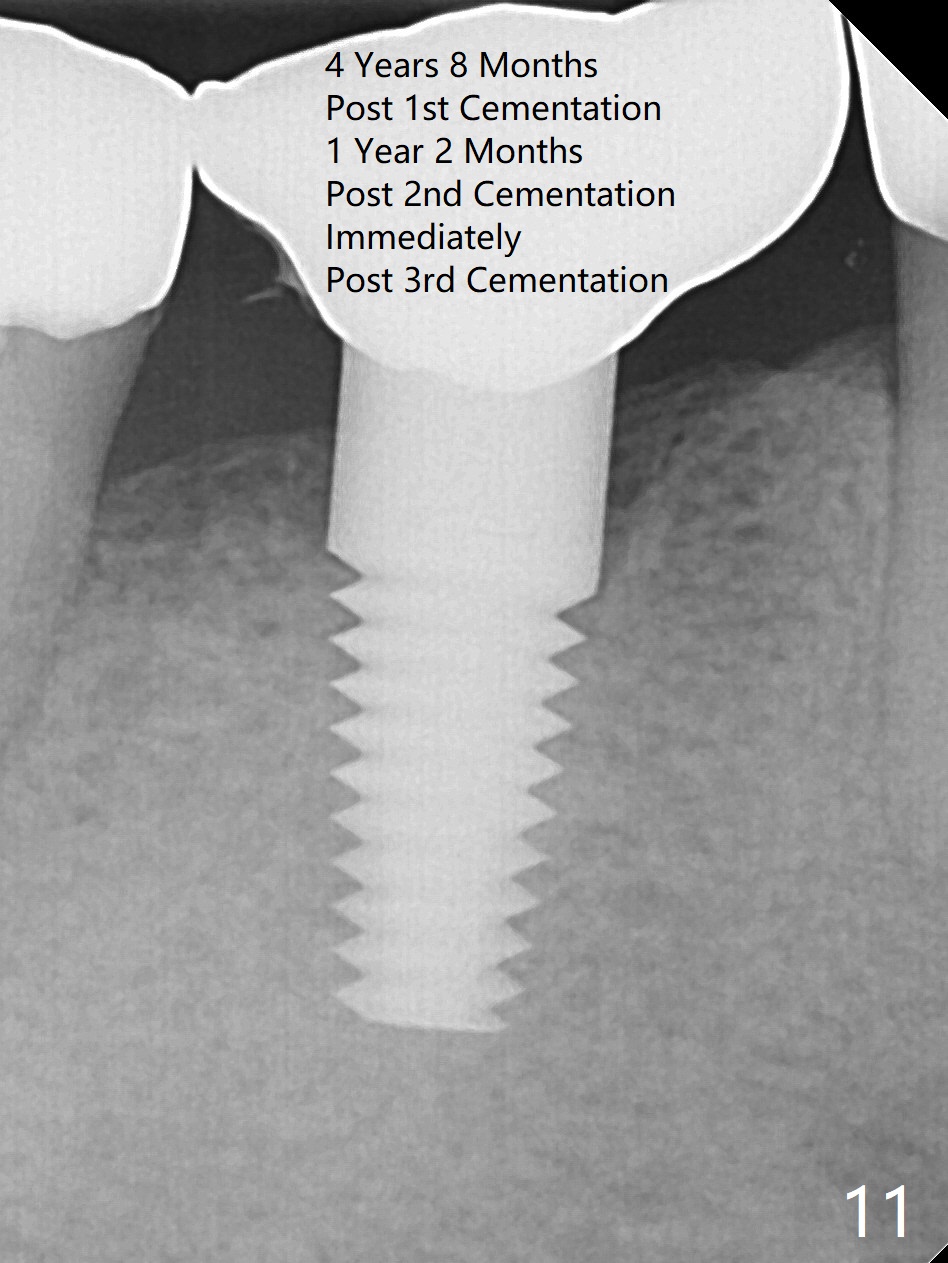

A 47-year-old man has history of bruxism, chipping porcelain from #29-31 FPD (Fig.1). Following sectioning the FPD, osteotomy is created (Fig.2: 5x14 mm drill) for placement of a 5x14 mm tissue-level implant (Fig.3,4). A 4x3 mm abutment (Fig.5 (lingual view) A) with 3 vertical slots (* for increased retention) is placed to retain periodontal dressing. The crown over the implant has dislodged 3 times over 28 months post cementation (Fig.6). It appears that the top of the abutment is too rounded. Clinical exam shows that the abutment height can be more, although the tooth #3 is supraerupted (Fig.7 (orthodontic intrusion is not indicated because of furca infection)).

Pre-impression photos show supraerupted #3 (Fig.7). Clearance is a little more than 1 mm between the mesiopalatal cusp of #3 (Fig.7 *) and the rounded abutment (Fig.8). Removal of the abutment turns out to be easy. Reduction is confined to the opposing tooth (slopes of the cusps). No occlusal reduction is done for the new abutment as mentioned above except for 2 retention grooves. One-mm reduction ring barely passes the occlusal clearance (Fig.9). No cement is applied to the abutment in case a longer abutment may be required. Bone density seems to remain the same or increase after cementation of a new crown (Fig.7). The redo crown remains in place 1 year post cementation.